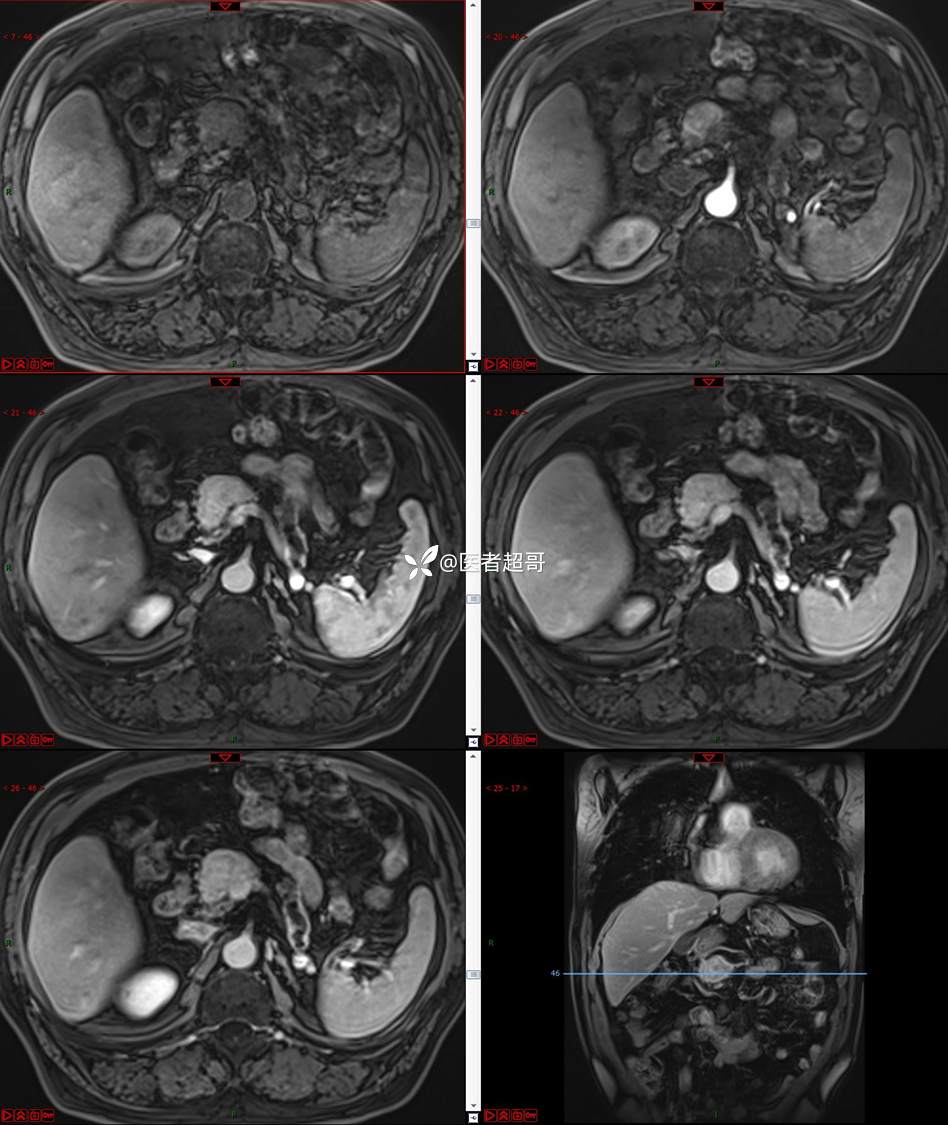

【影诊笔记677】查体发现胰腺占位性病变1周,细节决定成败,请诊断分析!

主 诉:查体发现胰腺占位性病变1周。

现病史:患者1周前在当地查体时发现胰腺占位性病变,无恶心、呕吐,无腹痛,无寒战、高热,无咳嗽、咳痰等异常不适,来我院门诊查上腹部CT平扫+强化:胰腺尾部异常密度灶。今为求进一步治疗,门诊以“胰腺占位性病变”收入院。患者自发病以来,一般情况可,神志清,精神可,普通饮食,二便正常,体重及体力无明显改变。

既往史:既往糖尿病病史2年,口服二甲双胍早晚各一片和格列吡嗪早晚各一片,否认高血压、心脑血管病等疾病史,否认肝炎、结核或其他传染病史及密切接触史,预防接种史不详,否认药物及食物过敏史,否认外伤史,12年前肾癌切除术手术史,否认输血史,其它无特殊。